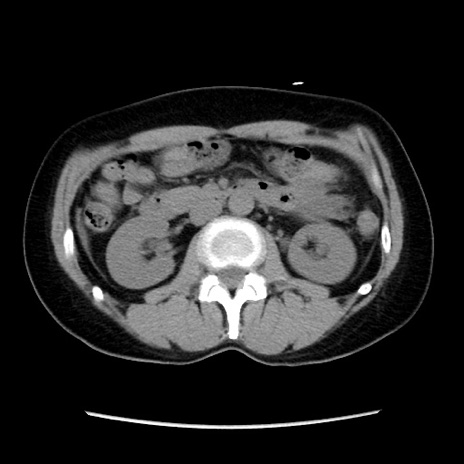

矢状断像

【症例】 50歳代女性

【主訴】 腹痛

【現病歴】前日生レバーを食べた。今朝に排便あり。 昼前に突然発症の腹痛を生じ、当院救急外来を受診した。

【既往歴】 子宮筋腫にてで子宮全摘後

【身体所見】 意識清明、腹部:平坦、軟、下腹部やや左を中心に圧痛・反跳痛あり、筋性防御あり

【データ】WBC 7800、CRP 0.07